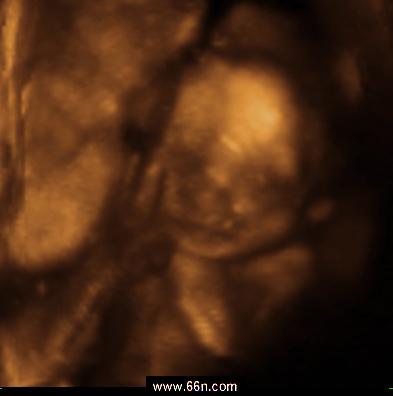

مكتبة صور الجنين بالألتراساوند منذ بداية الحمل وحتى نهايته

صور اخرى منوعة

مجموعة أخرى